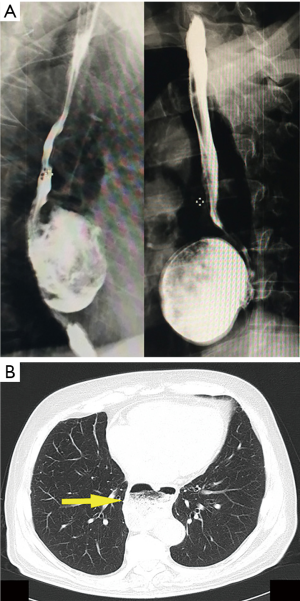

In the last two years, three consecutive patients were referred to our attention for the treatment of giant mid-esophageal diverticulum (mean size: 6.5±0.5 cm). The characteristics of study population were summarized in Table 1. All patients presented severe symptoms including dysphagia, regurgitation, gastro-esophageal reflux, food retention, weight loss and chest pain. All patients underwent standard pre-operative workup including barium swallow (Figure 1A), total body computed tomography scan (Figure 1B), manometry and 24-hour esophageal pH monitoring test. In all cases manometry showed an abnormal activity with diffuse esophageal spasm and impaired low esophageal sphincter (LES) relaxation.